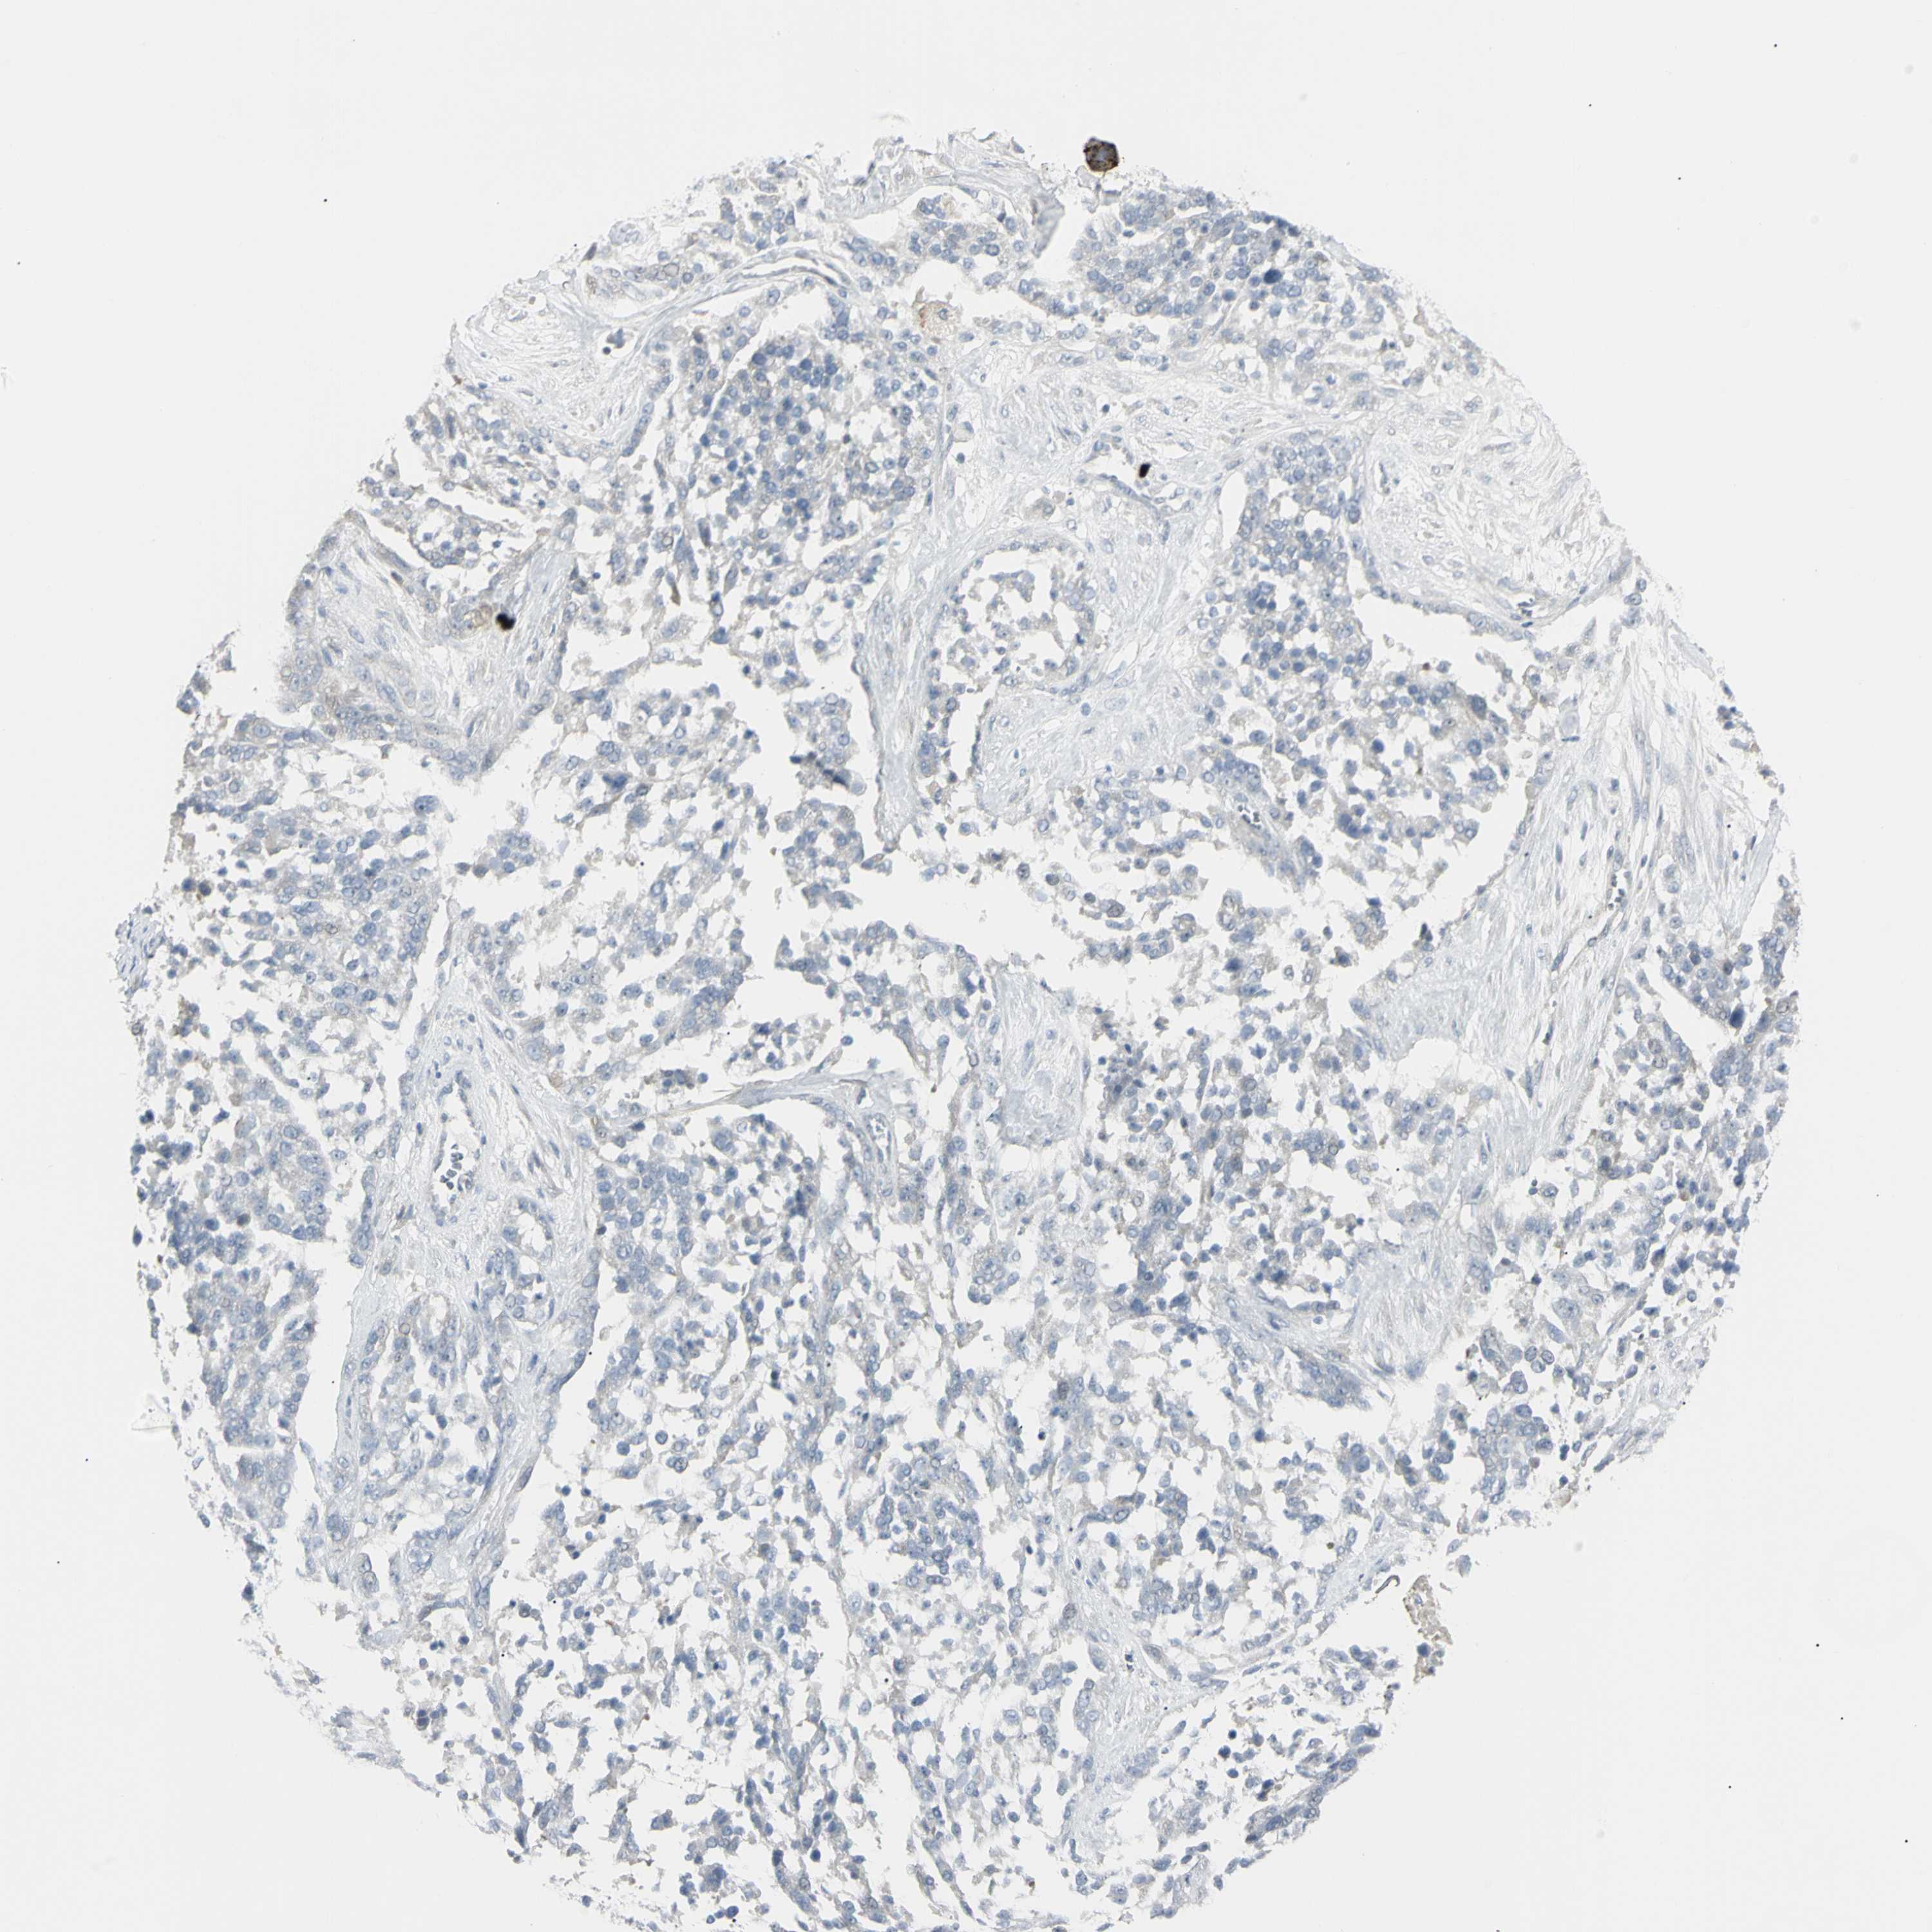

OVARIAN CANCER - Protein expressioni

A mouse-over function shows sample information and annotation data. Click on an image to view it in a full screen mode. Samples can be filtered based on level of antibody staining by selecting one or several of the following categories: high, medium, low and not detected. The assay and annotation is described here.

Note that samples used for immunohistochemistry by the Human Protein Atlas do not correspond to samples in the TCGA dataset.

Antibody stainingi

Antibody staining in the annotated cell types in the current human tissue is reported as not detected, low, medium, or high, based on conventional immunohistochemistry profiling in selected tissues. This score is based on the combination of the staining intensity and fraction of stained cells.

Each image is clickable and will lead to virtual microscopy that enables deeper exploration of all samples and also displays staining intensity scores, fraction scores and subcellular localization as well as patient and tissue information for each sample.

Antibody HPA009177

Antibody CAB002661

Cystadenocarcinoma, serous, NOS

Carcinoma, endometroid

Cystadenocarcinoma, mucinous, NOS

Carcinoma, NOS